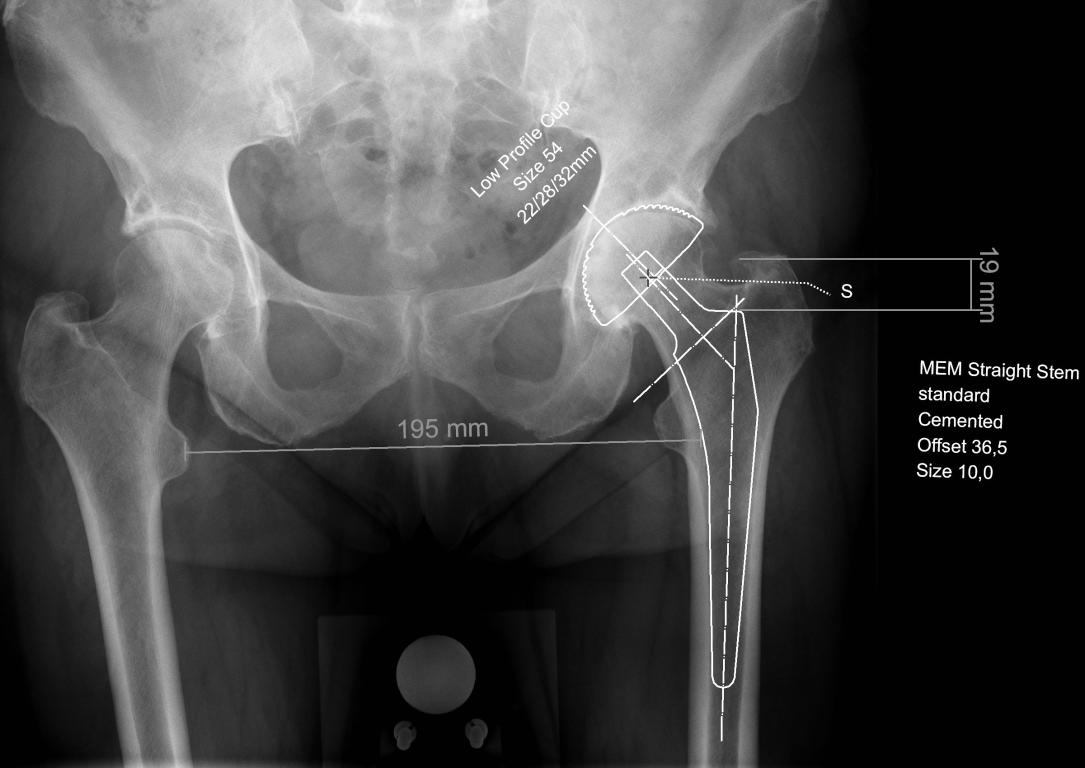

De totale heupprothese is een van de meest succesvolle operaties omdat het de vaak forse functionele beperkingen en pijnklachten ten gevolge van coxartrose kan doen verdwijnen. De fysiotherapeut heeft een belangrijke ondersteunende rol in het conservatieve en preoperatieve behandelingstraject, de indicatiestelling en het postoperatieve herstel. Daarnaast is het belangrijk om eventuele complicaties vroegtijdig te herkennen. Dit artikel beoogt inzicht te geven in de oorzaken van coxartrose, de indicatiestelling voor een totale heupprothese, de verschillende typen heupprothesen, de verschillende benaderingen en stappen tijdens de operatie, de nabehandeling en de mogelijke complicaties.

• kent u de verschillende typen heupprothesen